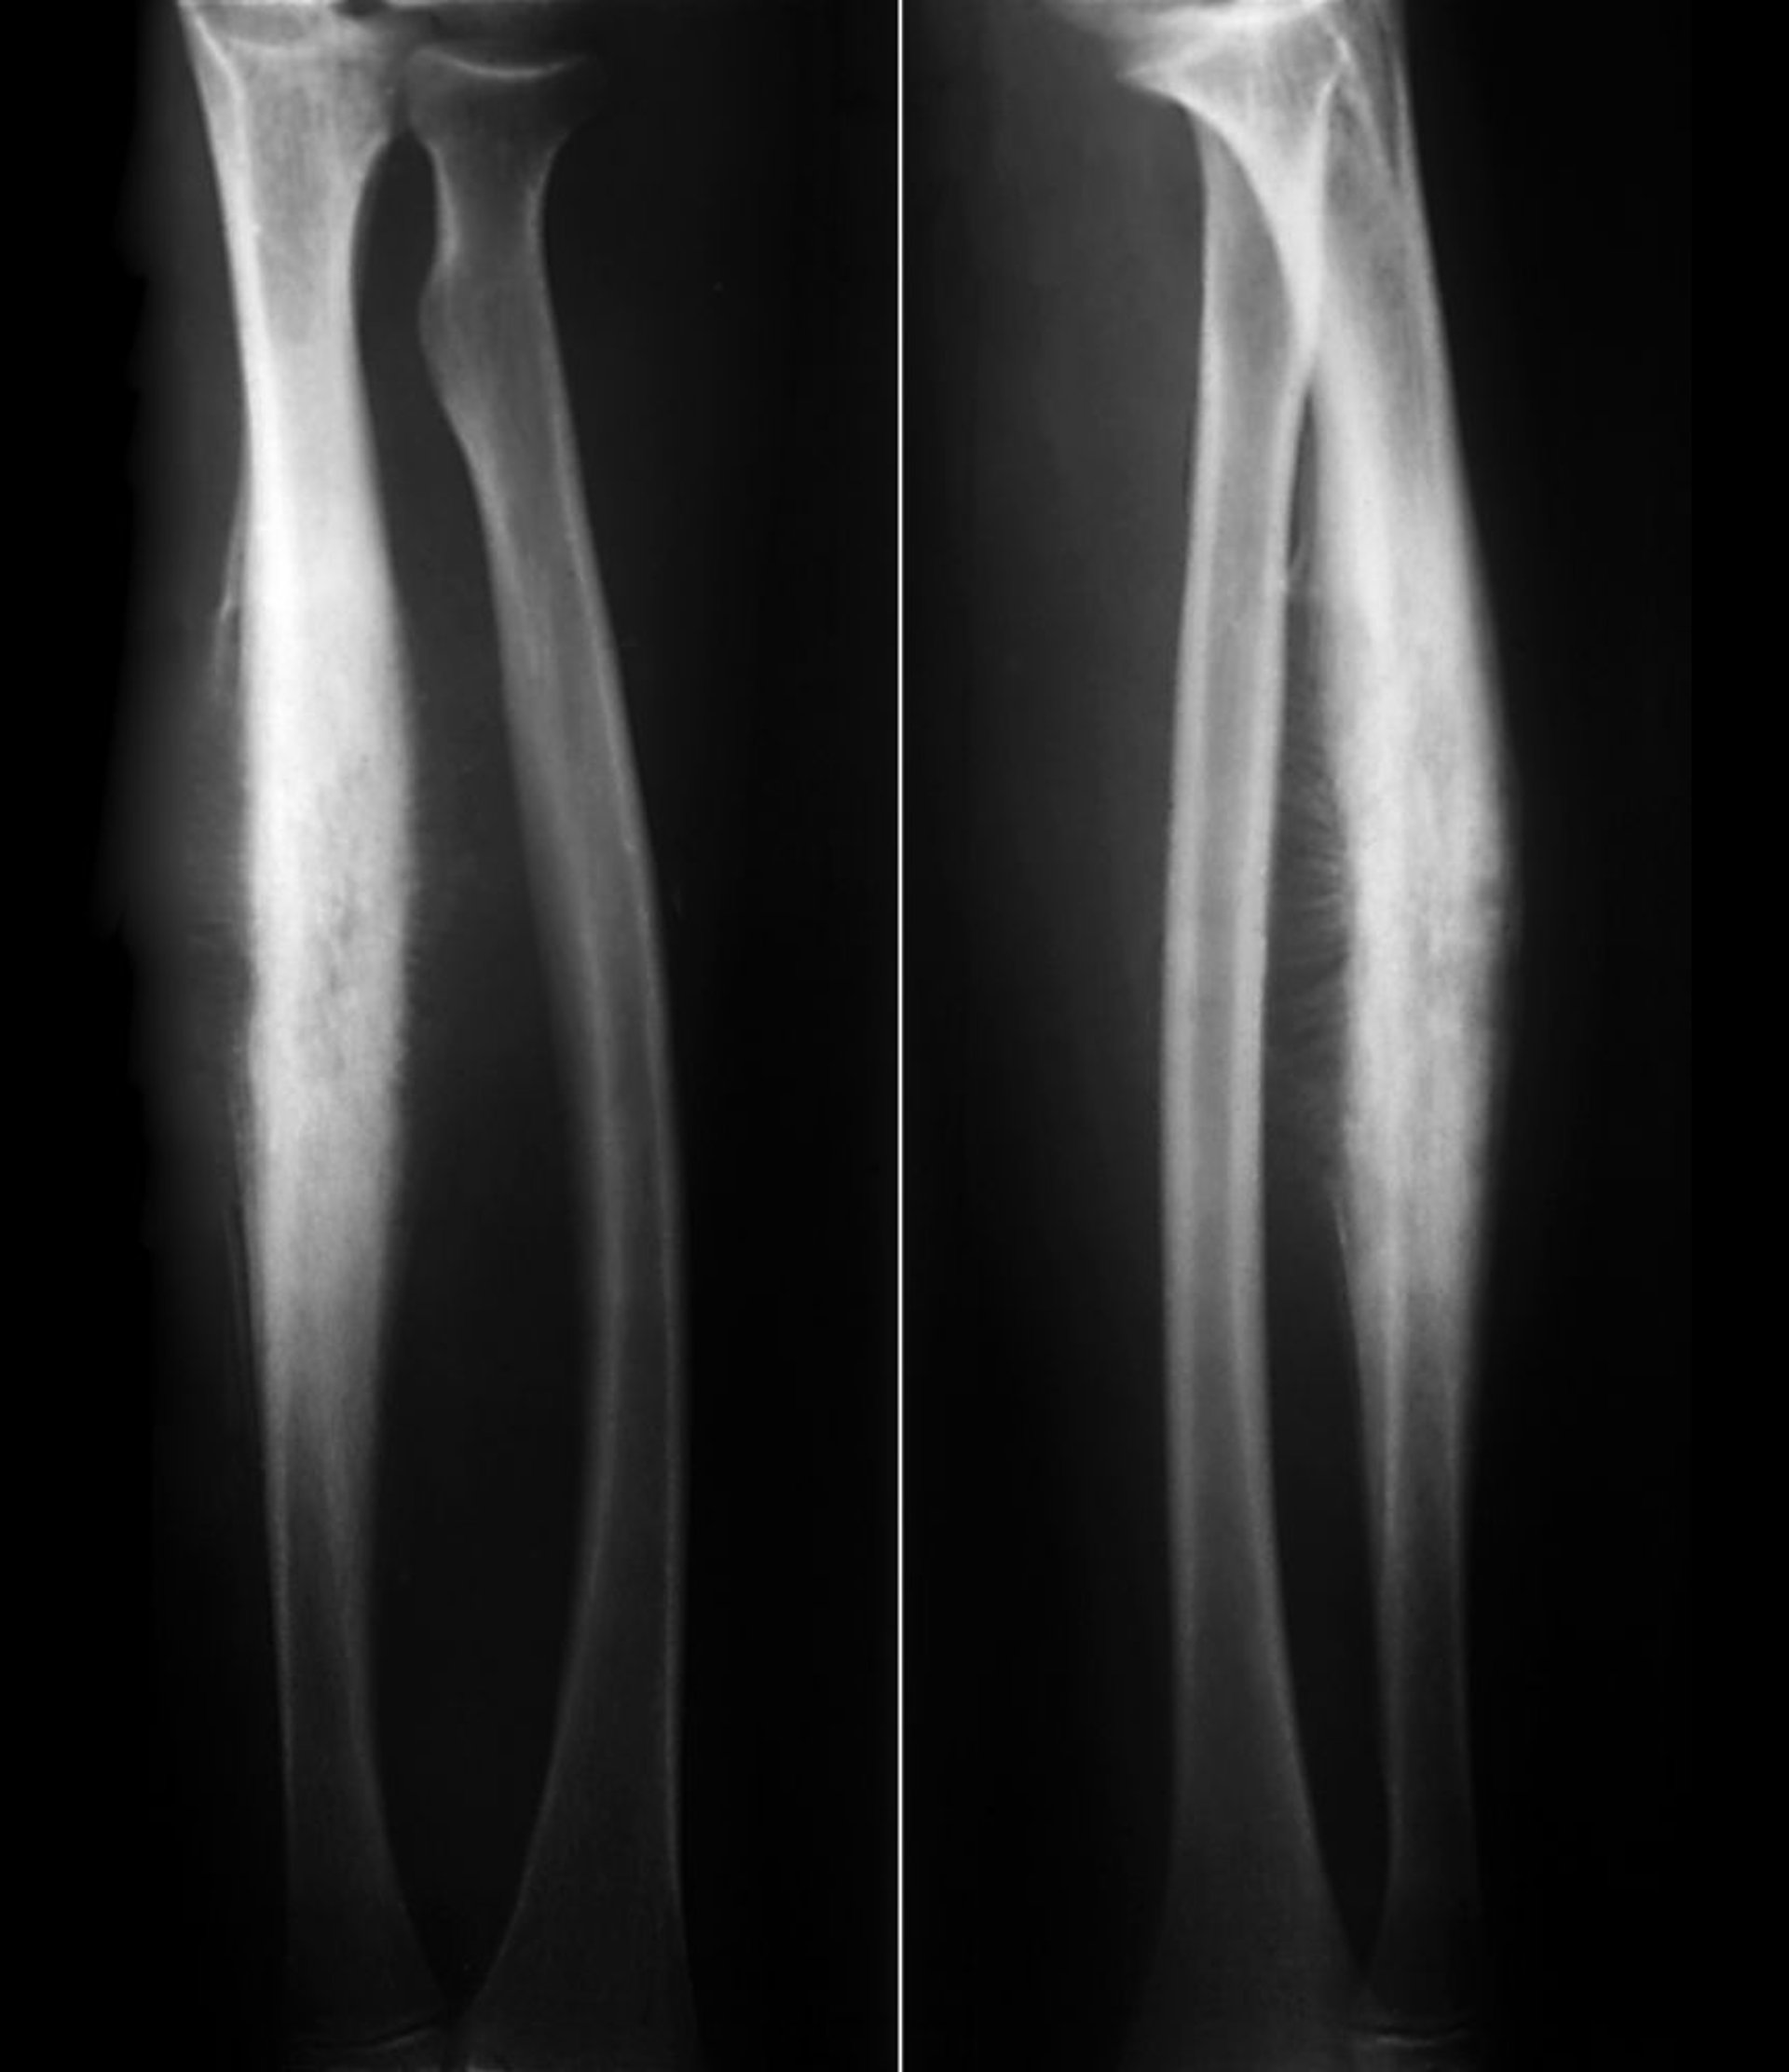

橈骨のユーイング肉腫

この橈骨骨幹部のユーイング肉腫は,骨膜下の反応性骨新生およびある程度の骨融解性の破壊像を示している。